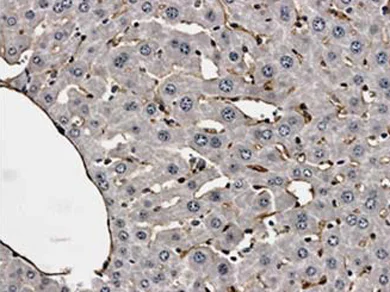

Immunohistochemistry (Formalin/PFA-fixed paraffin-embedded sections) - Anti-CD31 antibody [RM0032-1D12] - BSA and Azide free (AB56299)

ab56299 at 1/400 dilution, staining CD31 in LPS treated mouse liver tissue section by Immunohistochemistry (Formalin/PFA fixed paraffin-embedded sections).